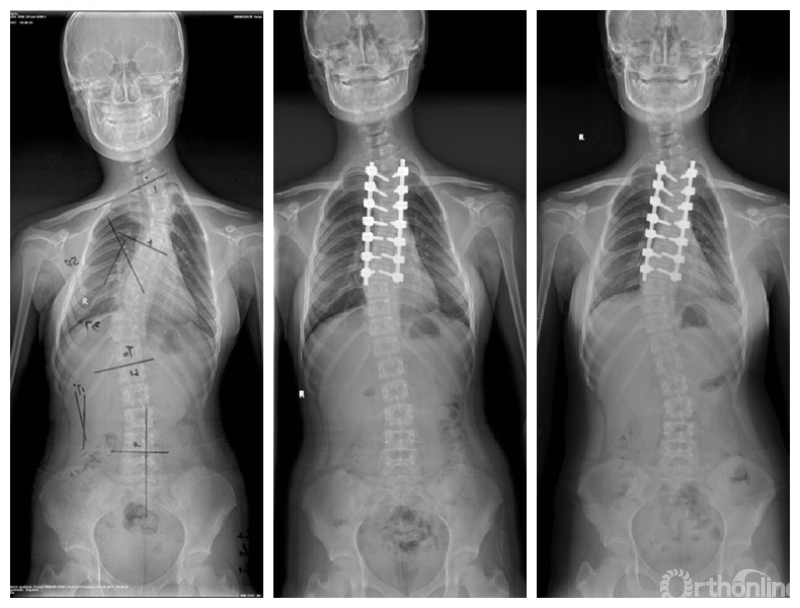

Wang等人[1]于2011年在Spine杂志上发表的文章中将远端附加现象定义为结构性主弯融合术后随访1年及以上时,主弯范围延长,最下固定椎(lowest instrumented vertebra,LIV)下方有更多椎体进入主弯,LIV以下第一个椎体偏离骶骨中垂线(center sacral vertical line,CSVL)5mm以上或LIV以下第一个椎间隙成角增加5°以上的现象。目前这一定义得到学界广泛的认可。远端附加现象多出现于行选择性胸弯融合的患者,主要是Lenke 1A型及Lenke 2A型AIS患者。其诊断标准为末次随访时,对比术后站立位脊柱全长正位片出现:

(1)主弯下端椎(lower end vertebra,LEV)向远端移动,主弯椎体数增加,LIV偏离CSVL 10mm以上;

(2)或是LIV以下第一个椎体偏离CSVL 5mm以上;

(3)或是LIV以下第1个椎间隙成角增加5°以上[1,2]。

最后实质触及椎是LIV的最佳选择[8]

国内邱勇教授团队[12]回顾性分析104例Lenke 1A型AIS患者,其中23例(22.1%)发生远端附加现象,分析认为LIV的选择应位于最后实质触及椎(从骶骨往头端最后一个被CSVL平分的椎体)以降低远端附加现象发生率。此外,李明教授团队[13-15]的系列研究也认为选择最后实质触及椎作为LIV,术后发生远端附加现象的风险最低,同时应该考虑LIV距离CSVL不应超过1cm。因此,学界认为对于AIS患者行选择性胸弯融合手术的LIV应选择最后实质触及椎最为合适。